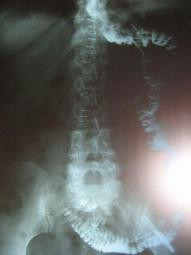

Post Image

Estudio radiológico previo a inicio de alimentación